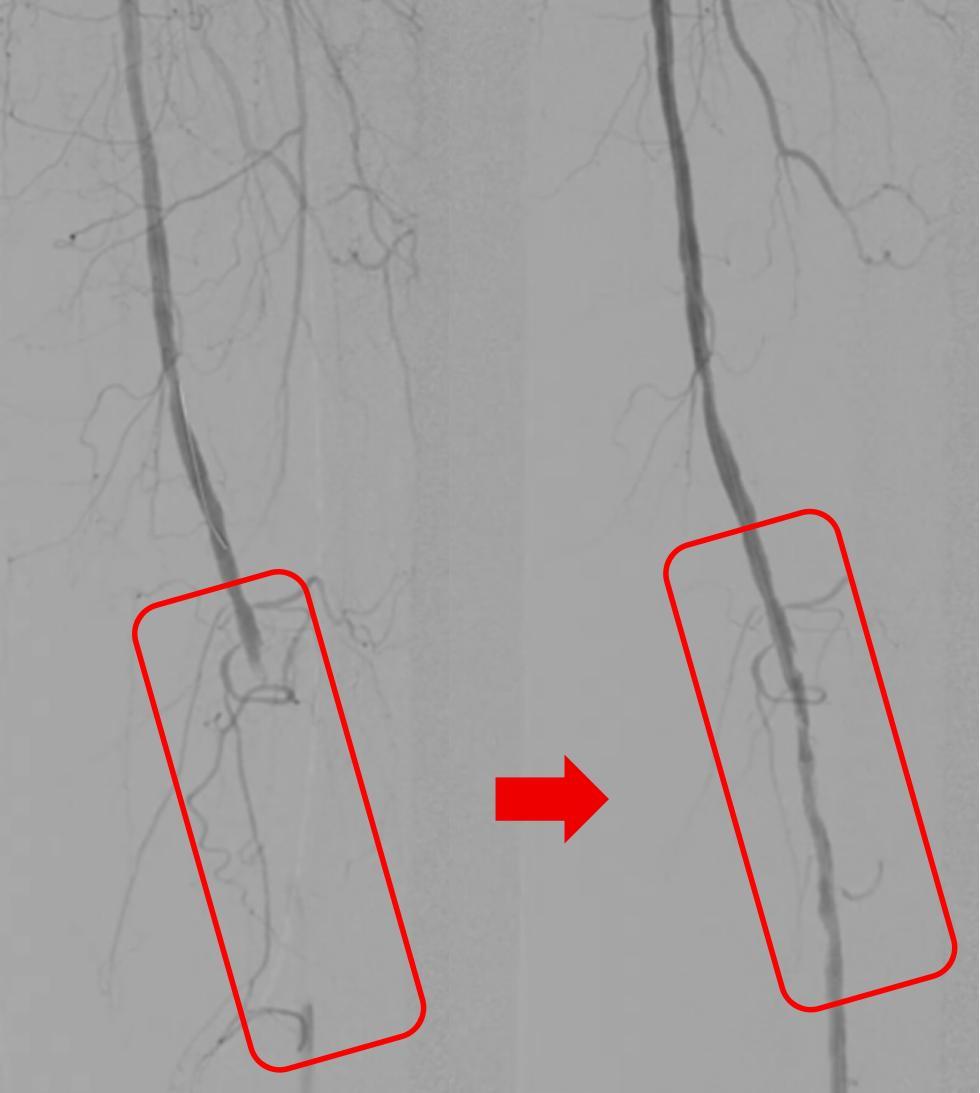

紅框內的下肢動脈血栓被清除